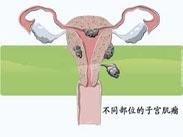

女性生殖道多部位原發癌

628健康網為您分享有關女性生殖道多部位原發癌的癥狀,女性生殖道多部位原發癌的治療方法,女性生殖道多部位原發癌的預防...